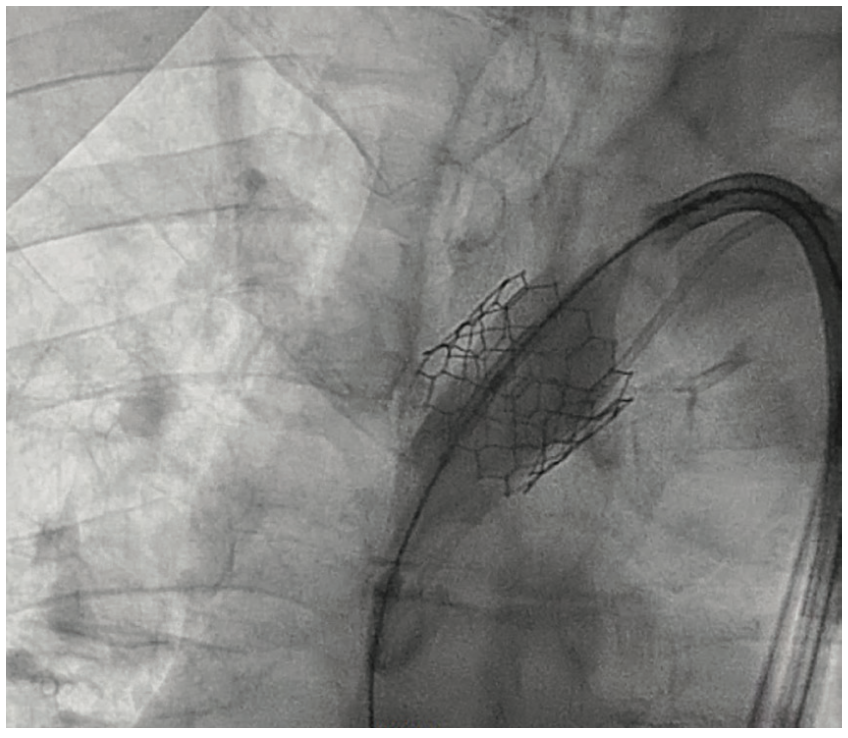

During the TAVR procedure, a Sapien 3 26 mm valve was loaded over a Safari wire (Boston Scientific) and advanced into the aortic annulus under fluoroscopy, with good planar angle positioning confirmed using contrast injection. After valve placement, rapid ventricular pacing was performed and the valve was deployed. However, immediately following deployment, the valve embolized into the ascending aorta. The valve was carefully pulled distally and secured just proximal to the origin of the right brachiocephalic artery. It was dilated with an extra 4 mL volume with two inflations performed. To confirm the patency of the right subclavian artery and the right brachiocephalic artery, access was subsequently obtained in the right radial artery, and no difference in the arterial pressure was noted as the catheter was advanced from the right radial artery into the aortic root. A second Sapien 3 26 mm valve was then loaded over the Safari wire and was similarly advanced into the aortic annulus under fluoroscopy, with good coplanar angle positioning confirmation via contrast injection. After rapid ventricular pacing, the second valve was deployed without issue. A post procedure aortogram confirmed good valve positioning, the absence of significant paravalvular leak, and patency of the left coronary artery. A limited echocardiogram also confirmed good valve positioning, the absence of paravalvular leak, and the absence of pericardial effusion. The patient tolerated the procedure well and left the cardiac catheterization laboratory in a stable condition. After chest x-ray confirmed stable positioning of the embolized valve in the ascending aorta, the patient was discharged on postoperative day one with a scheduled follow-up visit in three weeks.